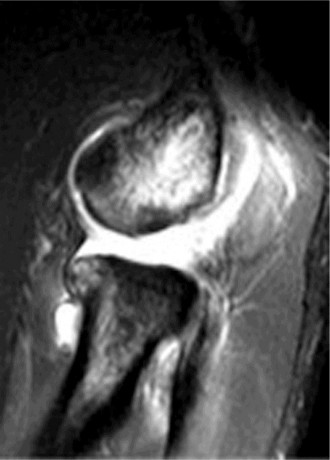

Examination reveals deformity about the elbow with no open lesions or skin tenting. He has a palpable radial and ulnar pulse and is neurologically intact. His images are shown (Figs. 2–85 to 2–88).

Figure 2–85

Figure 2–86

Figure 2–87

Figure 2–88

What is the diagnosis and direction of displacement?

- Monteggia fracture dislocation, posterolateral displacement of the forearm about the humerus

- Simple elbow dislocation, posterolateral displacement of the forearm about the humerus

- Transolecranon complex elbow dislocation

- Simple elbow dislocation, posteromedial displacement of the forearm about the humerus

Discussion

The correct answer is (B). This is the most common type of elbow dislocation, and often does not cause any osseous injury. Posterolateral and posteromedial dislocation account for approximately 90% of dislocations. Adequate pre- and postreduction films are necessary to evaluate for fracture, which would change the classification to a complex injury.